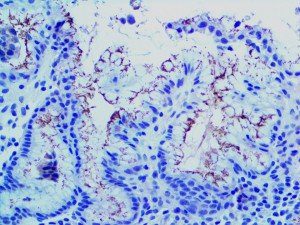

This activation induces inflammatory monocytes to highly express IL-6, starting a localized and then systemic cascade effect that results in hyperproduction of IL-6, which accelerates the inflammatory process. Because IL-6 also increases vascular permeability, excessive levels cause blood vessels to become very leaky. This, along with clotting factors released from vascular endothelial cells, stimulates the coagulation cascade, resulting in microthrombosis (tiny clots), which leads to ischemia and tissue death of the kidney, intestines, heart, liver, brain and extremities.